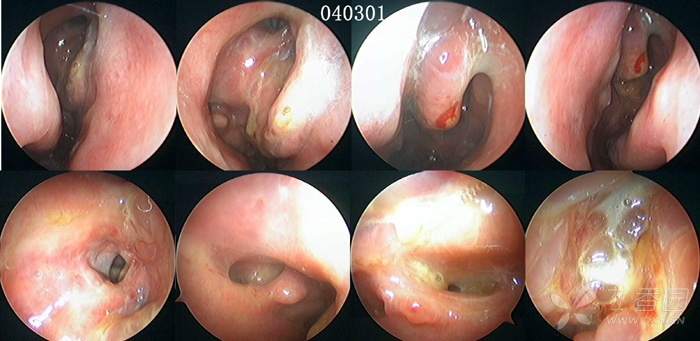

病例2:2004年2月12日手术,从手术创面的广泛性,到术后随访的频繁性,同样非常严重,站在今天鼻-鼻窦剔骨法成形术的角度,对于这样的做法和结果,既无法理解,更难以接受(见下图及图中的时间标示)。

首先,术后3-7天开始清理,之后每1-2周复诊一次,给予鼻内镜检查、清理,以及术后囊泡样变、炎症迁延、术腔粘连、窦口狭窄,对于绝大多数的患者而言,几乎就是一种常态。但频繁的内镜随访给患者带来的心理、经济、时间等各种压力,也使能够长期坚持随访者占比极少。因此,术后随访治疗能够坚持到完成粘膜上皮化的占比率,也受到了极大影响。